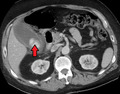

AcuteCholMark.png

Acute cholecystitis as seen on CT. Note the fat stranding around the enlarged gallbladder.